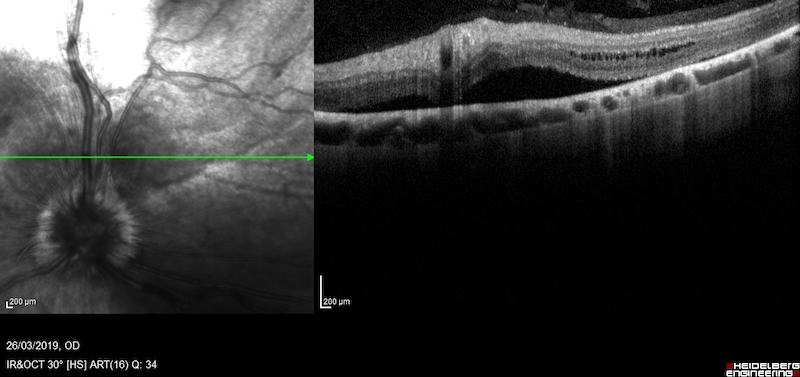

Pero hay determinados tipos de inflamaciones, especialmente de la coroides, que no se pueden ver bien con los signos clínicos externos. En estos casos hay que realizar pruebas especiales como la ecografía ocular, OCTs del segmento posterior o angiografía fluoresceínica.

Las uveítis posteriores suelen dejar en muchos casos zonas de degeneración de la retina, que también producen como secuela una pérdida de visión.